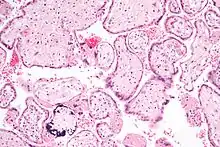

Micrograph of CMV placentitis. One cell on the image (centre) has the characteristic large nucleus with peri-nuclear clearing. Two cells (centre-right) have the characteristic (cytoplasmic) viral inclusion bodies (small pink globules). H&E stain.

CMV infection can be demonstrated microscopically by the detection of intranuclear inclusion bodies. On H&E staining, the inclusion bodies stain dark pink and are called "owl's eye" inclusion bodies.[45]

Micrograph of CMV placentitis.